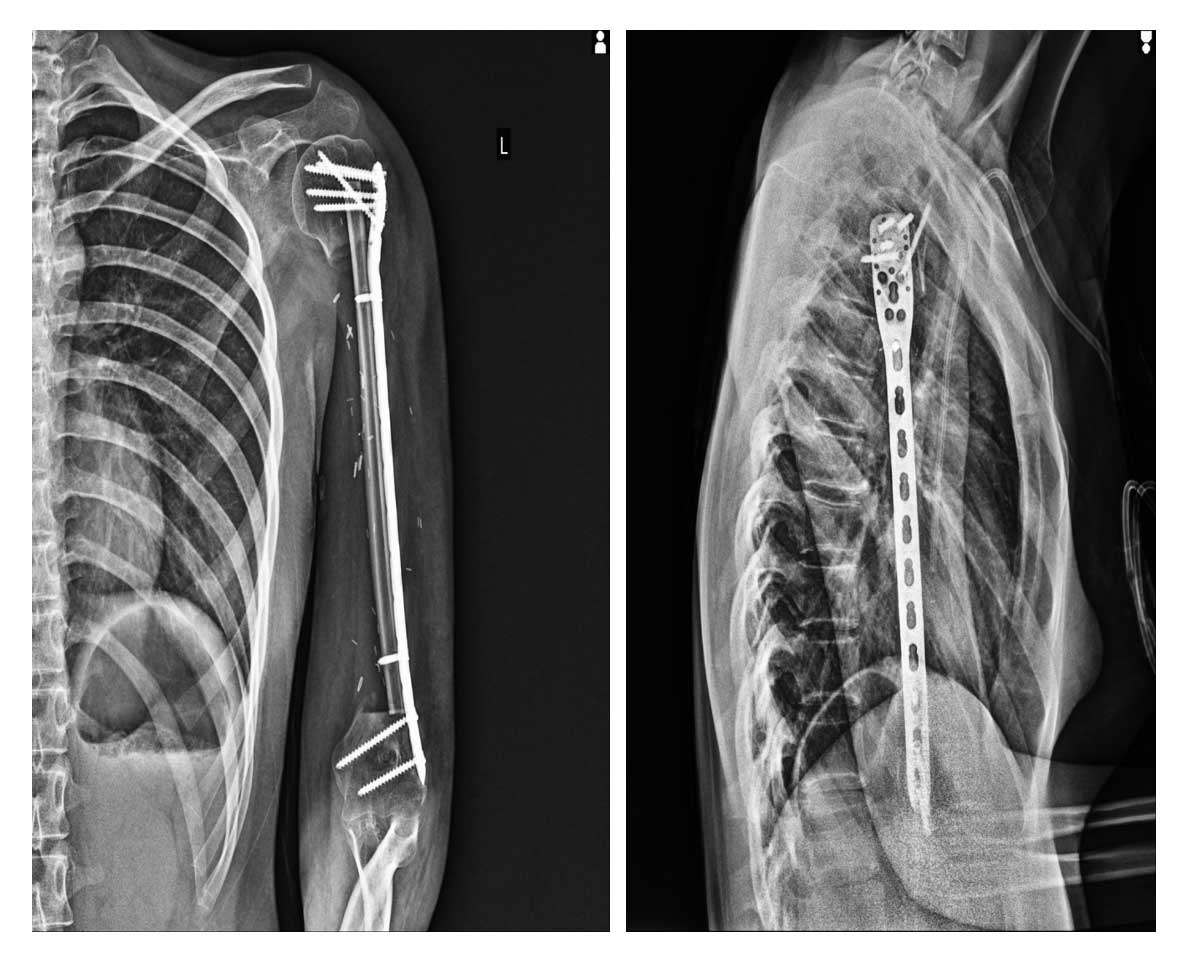

Kemoterapi tedavisi tamamlandıktan sonra hastaya geniş rezeksiyon uygulanmış, kemik bütünlüğünü yeniden sağlamak amacıyla vaskülerize fibula ile rekonstrüksiyon yapılmıştır. Düşük el fonksiyonunu düzeltmek için üçlü tendon transferi (pronator teres–extensor carpi radialis longus–palmaris longus transferi) gerçekleştirilmiştir.

Ameliyat Sonrası: Röntgende rezeksiyon sonrası uygulanan vaskülerize fibula ve plak fiksasyonu görülmekte.